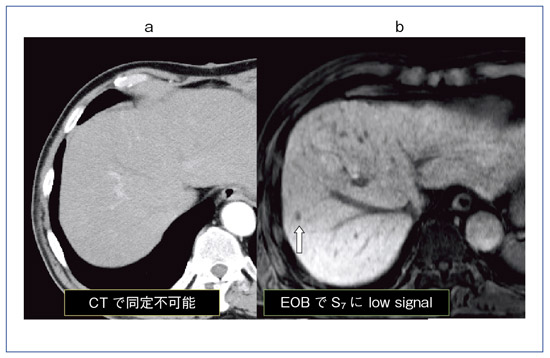

![[A12289094]肝の画像診断 第2版 画像の成り立ちと病理・病態 松井 修](https://auctions.c.yimg.jp/images.auctions.yahoo.co.jp/image/dr000/auc0507/users/d4fab30473777a8019148ae00533fa27693af6d4/i-img346x500-1720752504vsryrw371905.jpg)